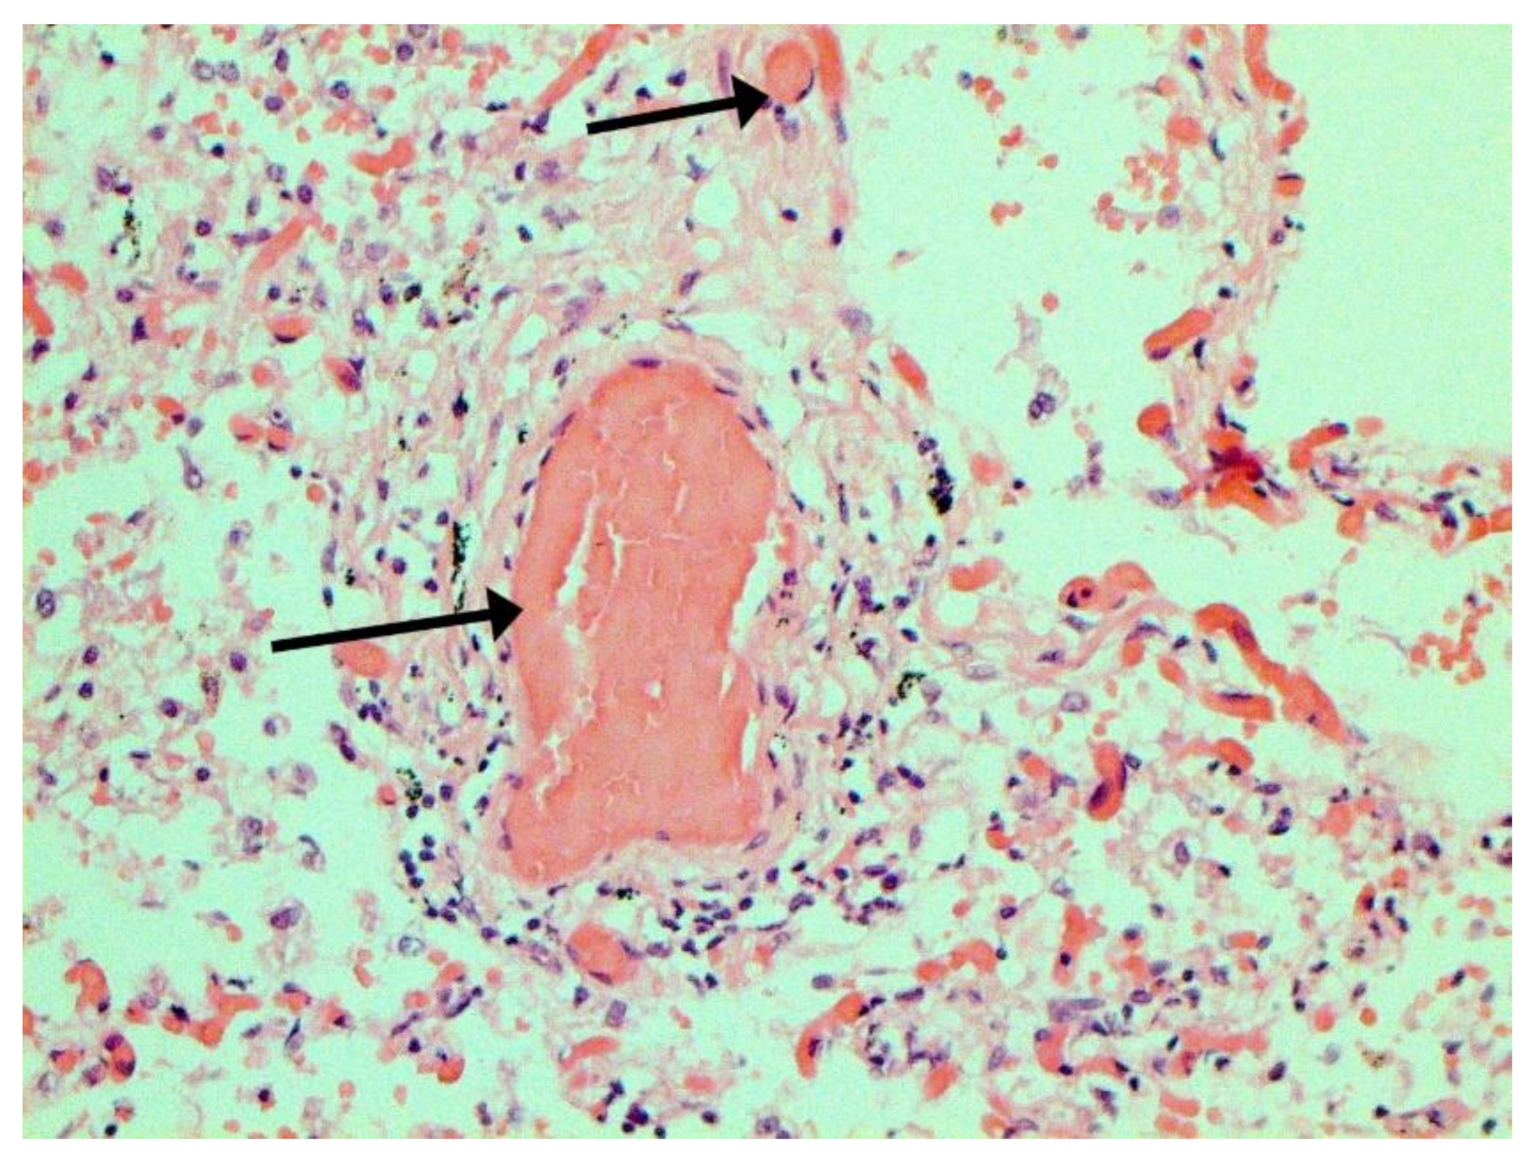

Figure 8.

Edema and perivascular hemorrhages in lung. H-E ×100.

The main morphological substrate of respiratory insufficiency is diffuse alveolar damage. The term viral pneumonia, widely used in the clinic, essentially reflects its development. In turn, severe diffuse alveolar injury is synonymous with the clinical concept of “acute respiratory distress syndrome” (ARDS). In the pathogenesis of ARDS, without a doubt, the most important role is played by the damage to the microcirculatory bed, the genesis of which requires further study, but direct viral damage is most likely. COVID- 19 is characterized by a pronounced fullness of the capillaries of the interalveolar septa, as well as branches of the pulmonary arteries and veins, with erythrocyte sludge, fresh fibrin, organizing blood clots, and intrabronchial, intrabronchiolar, and intra-alveolar hemorrhages, which are a substrate for hemoptysis, as well as perivascular hemorrhages (Figure 8). Pronounced alveolar hemorrhagic syndrome is characteristic of most cases, up to the formation, in fact, of hemorrhagic infarcts (although true hemorrhagic infarcts are not uncommon). Pulmonary blood clots are important to distinguish from thromboembolism, as pulmonary embolism (PE) is also characteristic of COVID-19. Thrombosis of the pulmonary arteries sometimes progresses to the right parts of the heart, and thrombosis of the arteries of various organs with the development of their infarcts (myocardium, brain, intestines, kidneys, and spleen) is described. This distinguishes changes in the lungs in COVID-19 from those previously observed in influenza A/H1N1. Despite the pronounced hemorrhagic syndrome, significant deposits of hemosiderin are not observed.